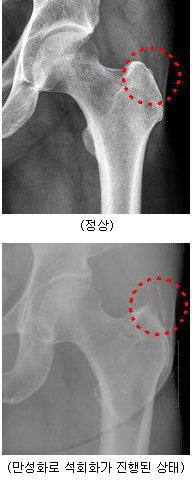

대둔 점액낭염은 달리기를 하는 사람들에게 많이 볼 수 있는데, 오래 서서 일하는 직업을 가진 사람들에서도 흔히 볼 수 있다. 엉덩이 부위에는 근육들이 있는데 이 근육들이 과도하게 마찰을 일으키게 되면 염증이 발생하게 된다. 초기에는 약간의 염증액이 고이는 정도이지만 만성화되면 점액낭의 막 자체가 두꺼워져서 마치 큰 물주머니가 있는 것처럼 되고 이런 경우 단순한 물리치료나 약물치료로는 효과가 없게 된다. 경우에 따라 마찰이 심해져 부분적인 파열이 일어나게 되고, 심한 통증과 질환의 만성화가 초래되기 때문에 주의가 필요하다.

엉덩이 관절은 무릎관절에 비해 비교적 단순한 구조로 되어있지만 큰 근육들이 서로 마주보고 있으며, 상체의 체중을 받아 하체로 연결하는 중요한 역할을 하기 때문에 근육의 마찰로 인한 염증이 생기기 쉽다. 하지만 이러한 점액낭염은 X-ray 검사에서 나타나지 않기 때문에 자세한 진찰을 하지 않으면 쉽게 진단을 내리기가 어렵고, 증상이 허리 디스크에서 발생하는 방사통과 비슷하기 때문에 허리 디스크로 오인되는 경우가 많다. 실제로, 엉덩이 부분의 통증을 호소하는 경우 대퇴골두의 무혈성 괴사라든가 고관절의 퇴행성 관절염 같은 관절 자체의 질환보다는 이 관절을 지탱하는 주변 근육 사이에 발생하는 점액낭염으로 인한 통증이 더 많음에도 불구하고, 적지 않은 사람들이 병원에서 별다른 이상이 없다는 얘기를 듣거나 혹은 허리 디스크라는 진단을 받고 증상의 호전 없이 답답해하고 있는 것을 볼 수 있다.